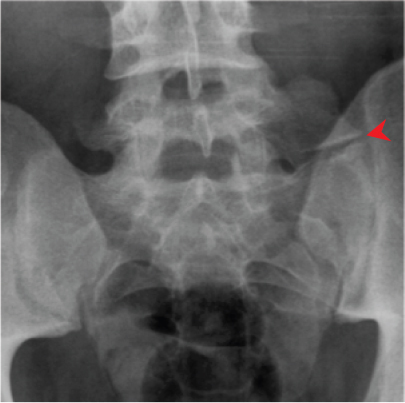

Symptoms related to ligamentum flavum buckling usually only occur when the spine is straight. Thoracic and Lumbar Spine | Radiology Key

Ten patients who underwent operation for compression of spinal nerve roots by the ligamentum flavum were followed for five years. Lumbar Spinal Stenosis

One common component of lumbar spinal stenosis is thickening of the ligamentum flavum. Symptoms related to ligamentum flavum buckling usually only occur when the spine is straight. The ligamentum flavum originates bilaterally at the articular processes on either side of the nerve roots and extends posteriorly along the lamina to midline. The ligamenta flavum is a short but thick ligament that connects the laminae of adjacent vertebrae from c2 to s1 and is considered a medial ward . Medical definition of ligamentum flavum: However, the etiology and pathophysiology of this . Ossification of the ligamentum flavum of the spine (olf) is rarely reported in individuals of european ancestry. That's because when the back is bent, the ligament stretches and .